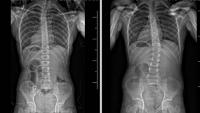

Pediatric Orthopedics and Spine at Columbia and NewYork-Presbyterian Morgan Stanley Children's Hospital is recognized as one of the top programs in the country for their specialized expertise across the full spectrum of orthopedic conditions affecting infants, children, and adolescents, including:

- Spine Disorders and Scoliosis

The specialists in our orthopedic clinic are highly skilled in providing young patients with state-of-the-art surgical and non-surgical treatments for the entire spectrum of pediatric musculoskeletal disorders and injuries, including: lower extremity deformities, neuromuscular disorders and cerebral palsy, spinal deformity and scoliosis, leg length differences, hip dysplasia, orthopedic tumors, and sports injuries. Whether your child needs to see a non-operative specialist, or a pediatric orthopedic surgeon, we take a holistic view of each child's musculoskeletal system, caring for their specific developmental needs and getting them back to their most important job: being kids!